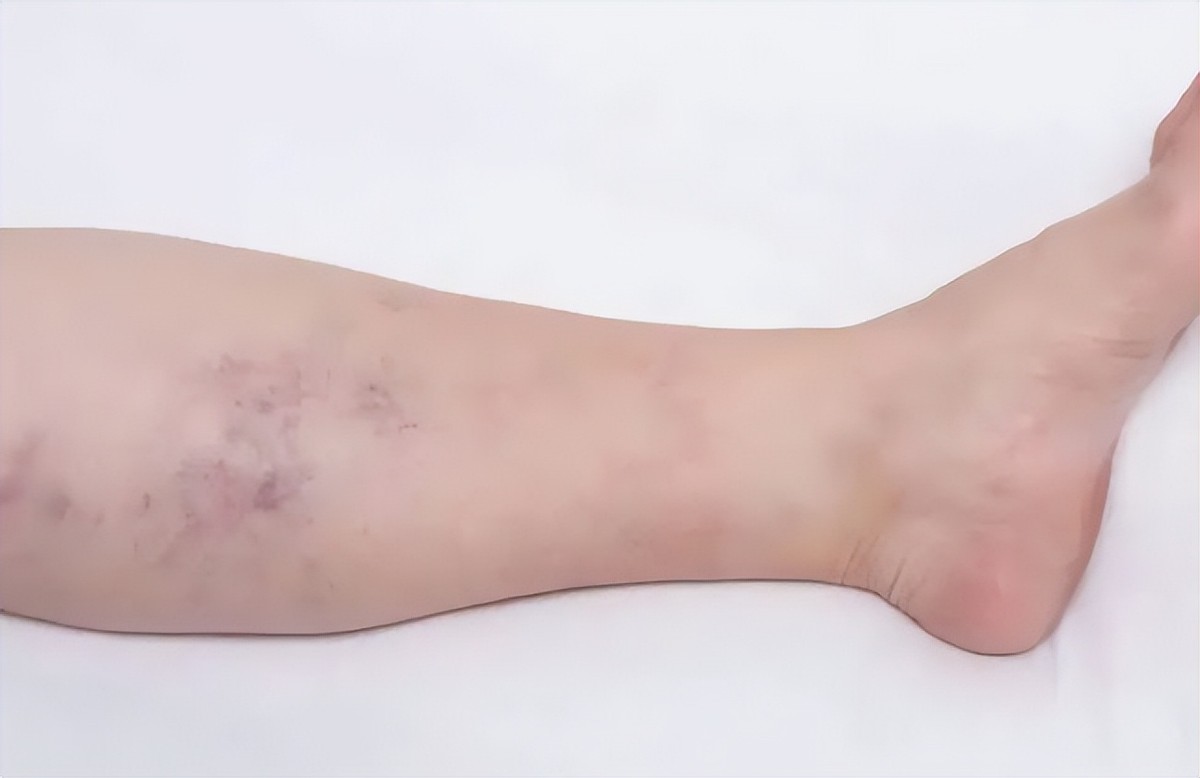

李明鑫在学校上体育课的时候,突然感觉腿部疼痛难忍。

老师还以为是活动的时候不小心伤到了,于是就检查了一下。结果却发现她的腿上全都是瘀青,就像被别人打了似的。老师赶紧联系了李明鑫的家长,让他们带着孩子去医院治疗。